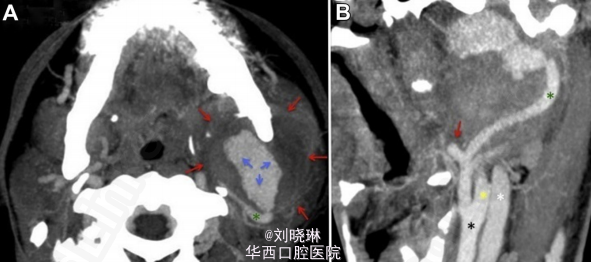

巨大的颈外动脉假性动脉瘤导致下颌骨髁突骨折

假性动脉瘤指动脉管壁被撕裂或穿破, 血液自此破口流出而被主动脉邻近的组织包裹而形成血肿,多由于创伤所致。动脉瘤囊壁破裂可能会导致大量出血,严重甚至能威胁生命。病人因外伤进行骨折固定四周后,左面部开始肿胀,发热。造影后发现左侧下颌升支附近存在一巨大的假性动脉瘤。